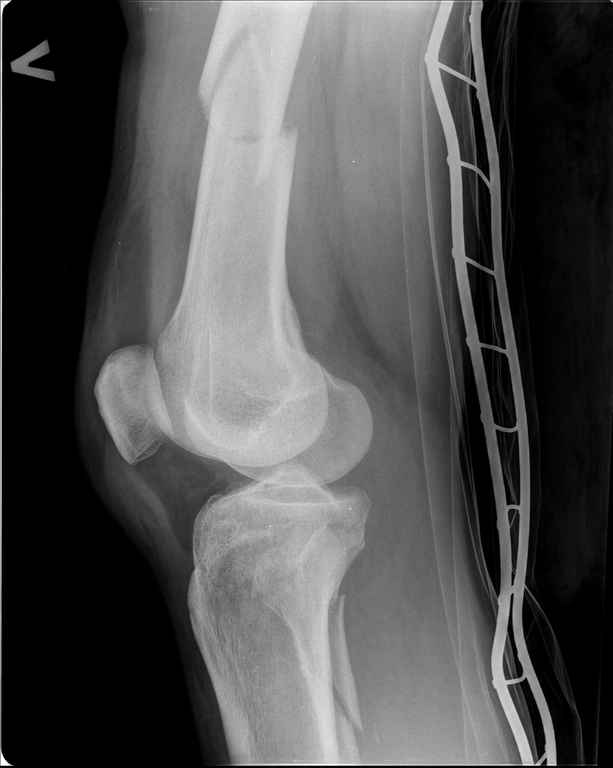

Ds: ТСТ. ЗЧМТ. СГМ. ЗТГК. О/фрагментарный перелом левого бедра. З/оскольчатый перелом с\3 левого плеча. Перелом левого локтевого отростка. З/перелом наружного мыщелка б/берцовой кости в/3 м/берцовой кости левой голени. при поступлении, ПХО раны левого бедра( рана 1х1см по наружной поверхности бедра в с/3) налажено скелетное вытяжение , и гипсовая лонгета на левую в/конечность. Находился в реанимации. 17.02.11 был прооперирован: БИОС левого плеча, о/синтез левого локтевого отростка по Веберу, БИОС левого бедра (длинная версия Fi-Can Sanatmetal диаметр 10мм), мыщелок голени трогать не стали. при остеосинтезе бедра возникли трудности при закрытй репозиции перелома в н/3, в связи с чем решили открыться внизу , отрепонировали без особого труда и выполнили блокирование во фронтальной плоскости 3-мя винтами + 1 винт спереди гвоздя (промазал). Убрал костодержатель, все нормально, контроль ЭОПом стояние отломков нормальное, зашились. На контрольной R-мме на утро выявлено вторичное смещение дистального отломка. Левая нога по сравнению со здоровой удлиннена до 2,5см( это за счет вальгусной установки гвоздя в проксимальном отделе, боялся свалиться на варус). Теперь думаем как поправить положение отломков в н/3, и зафиксировать так чтобы не съехало. Наше предложение расшиться в н/3 бедра, разблокироваться, перелом отрепонировать вновь и установить 1или 2отклоняющих винта в сагитальной плоскости, затем заблокироваться во фронтальной плоскости снова. Помогите советом, как выйти достойно из сложившейся ситуации. Заранее спасибо.